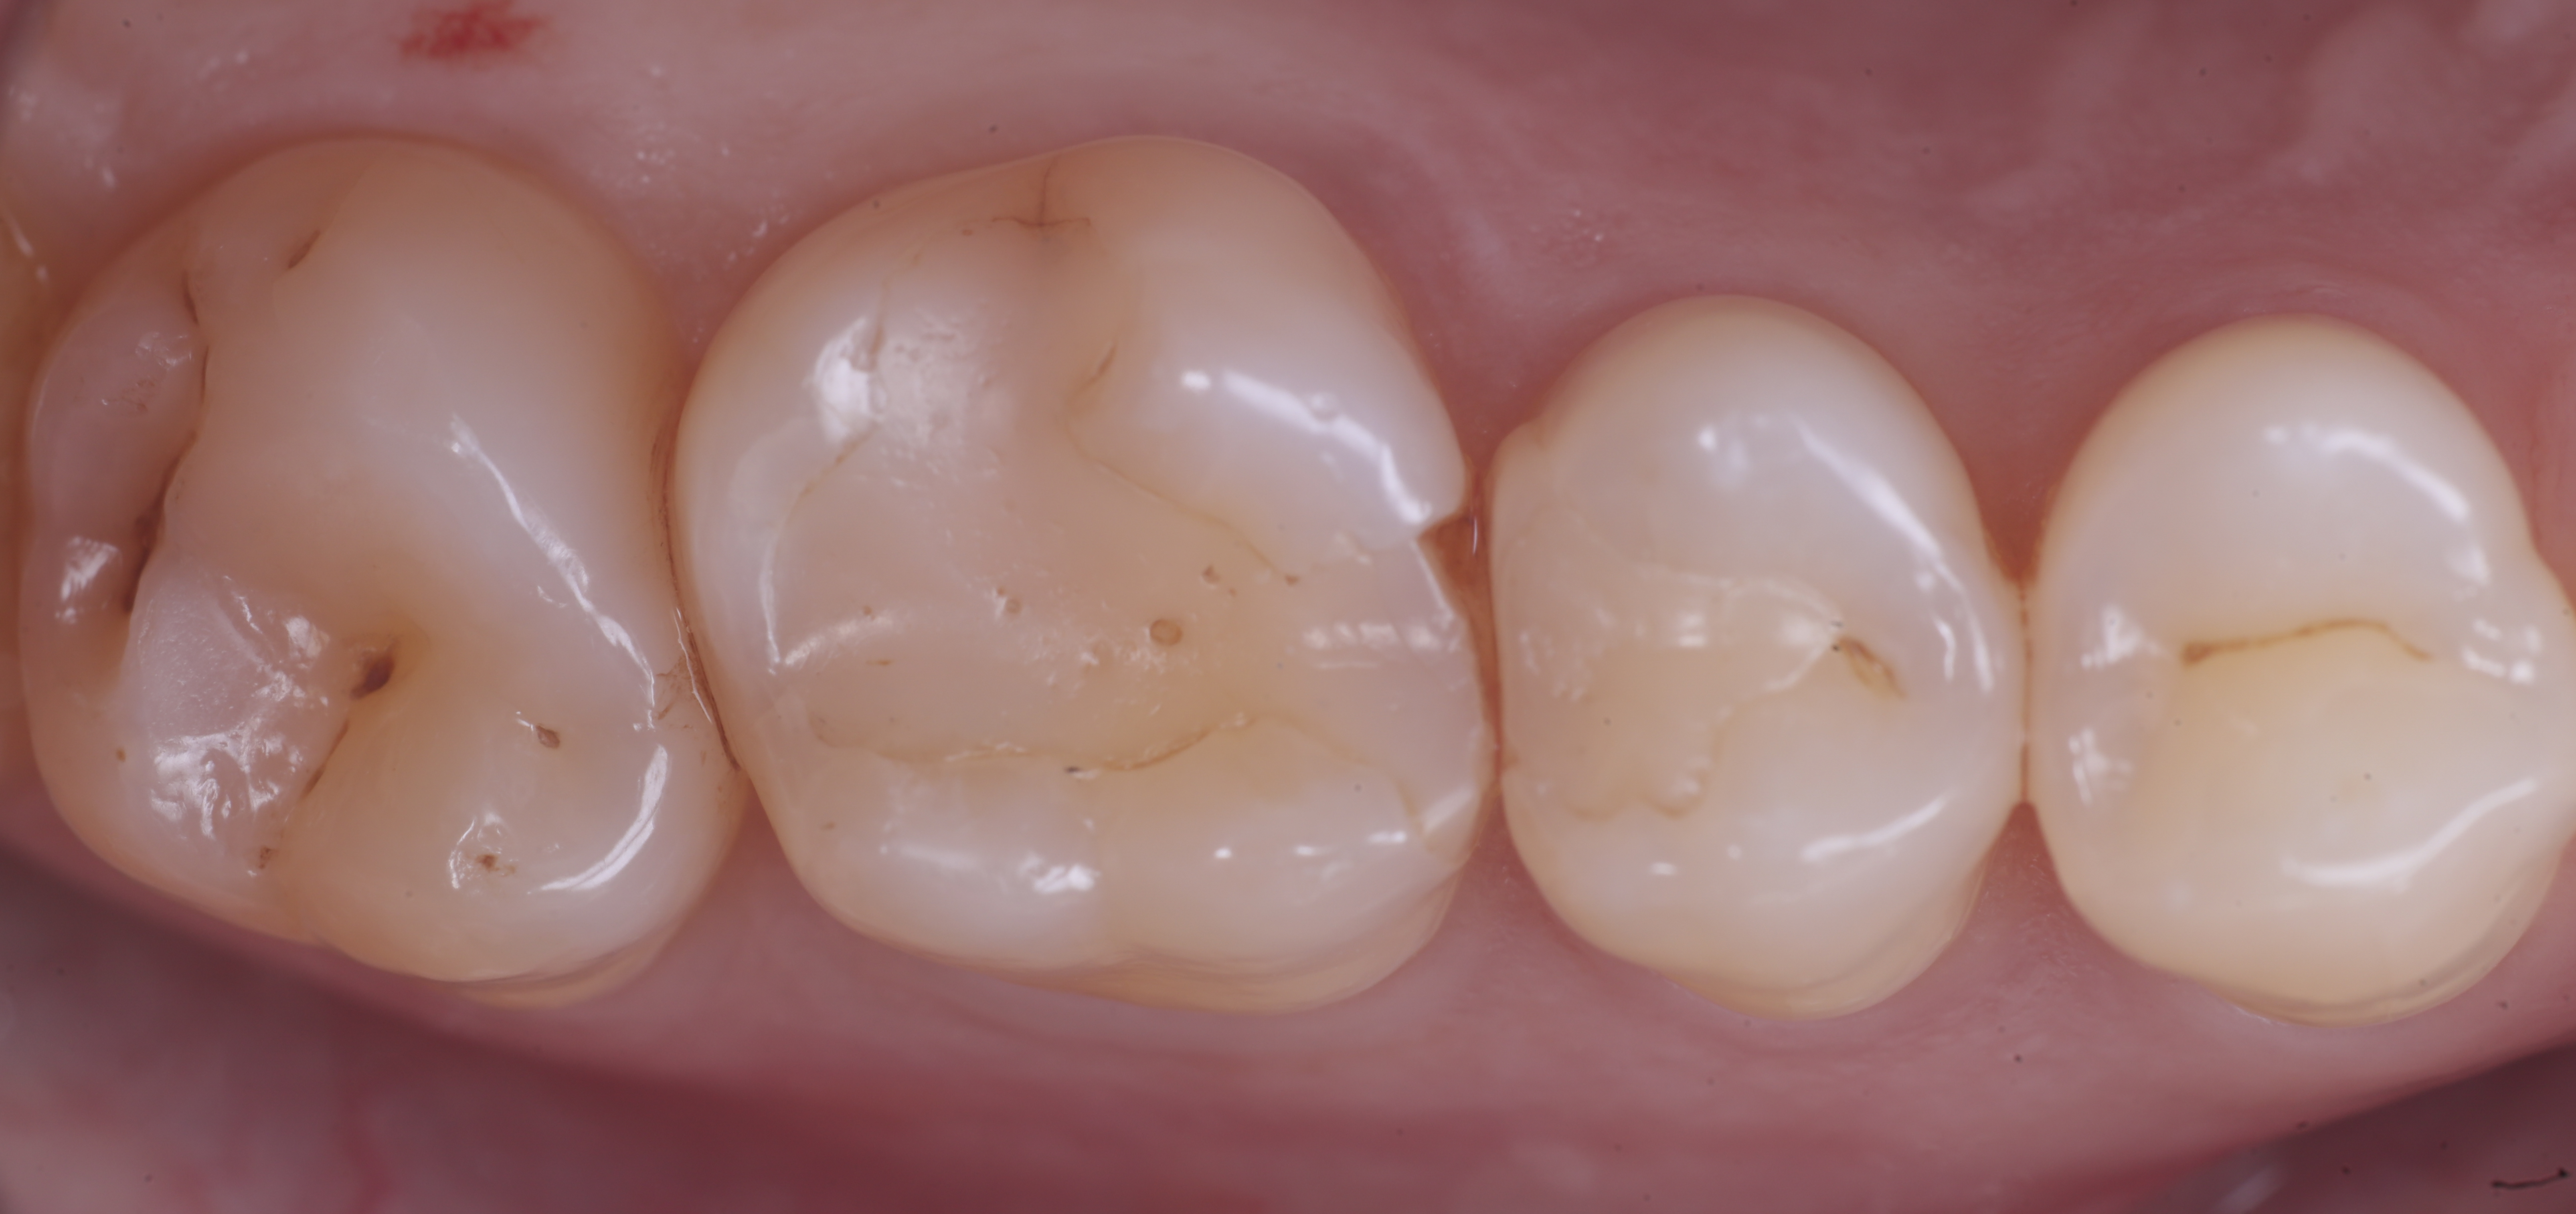

foto 3 Aspetto vestibolare della cavità ultimate

Una volta eliminato completamente il composito, si procede con la detersione della dentina con frese multilama ed alla rifinitura dei margini di smalto che dovranno essere robusti e puliti.